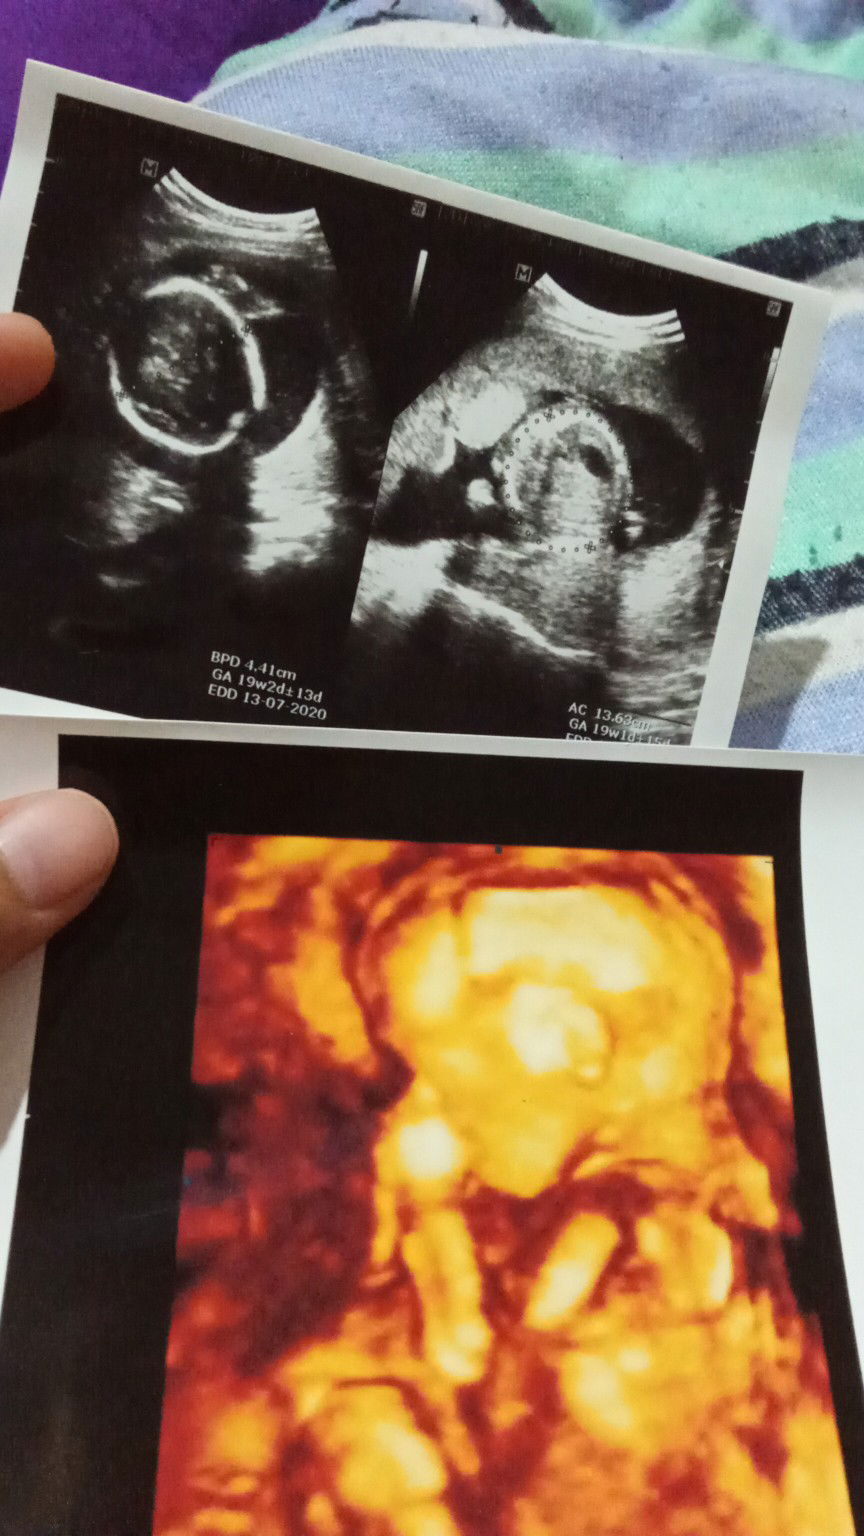

19w4d

disini ada ngga ya bun hpl bulan juli yg udh prnh usg . sy kmarin hbis usg tp jenis kelaminnya blm keliahatn kira2 usia brpa bulan normalnya jenis kelamin bisa diliat